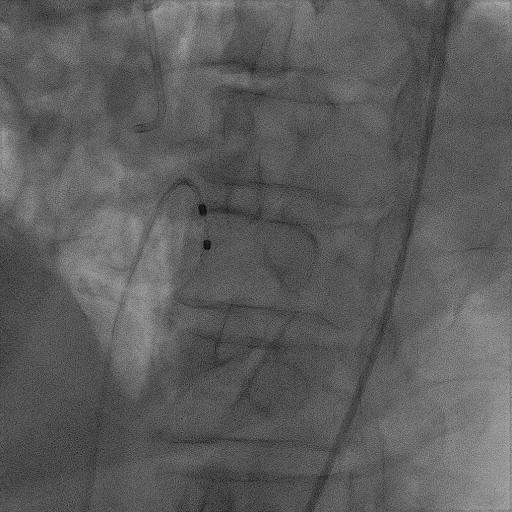

术前超声评估

术前超声诊断

LVOT-color:MR(重度),返流面积11.3cm2

肺静脉血流频谱呈收缩期反向

3D-color MV view:血流主要来源于2、3区

Qlab软件勾画估测瓣口面积约:6.16cm2

TEE LVOT切面返流量评估

TEE 4-Ch view返流量评估